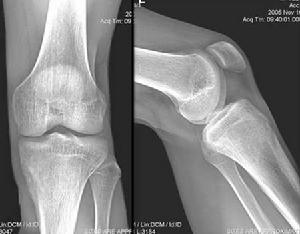

骨样骨瘤于1935年由Jaffe首次报告,是一种良性成骨性疾患,其发病率占骨肿瘤的2%~3%,多发生于长管状骨,约50%~60%发生在股骨和胫骨,少数发生在全身其他骨,肿瘤直径一般不超过1.5cm,接近2/3的病例以持续疼痛为主要症状,具有界限清晰的局灶性病灶,周围可有较大的骨反应区服水杨酸制剂可止痛。